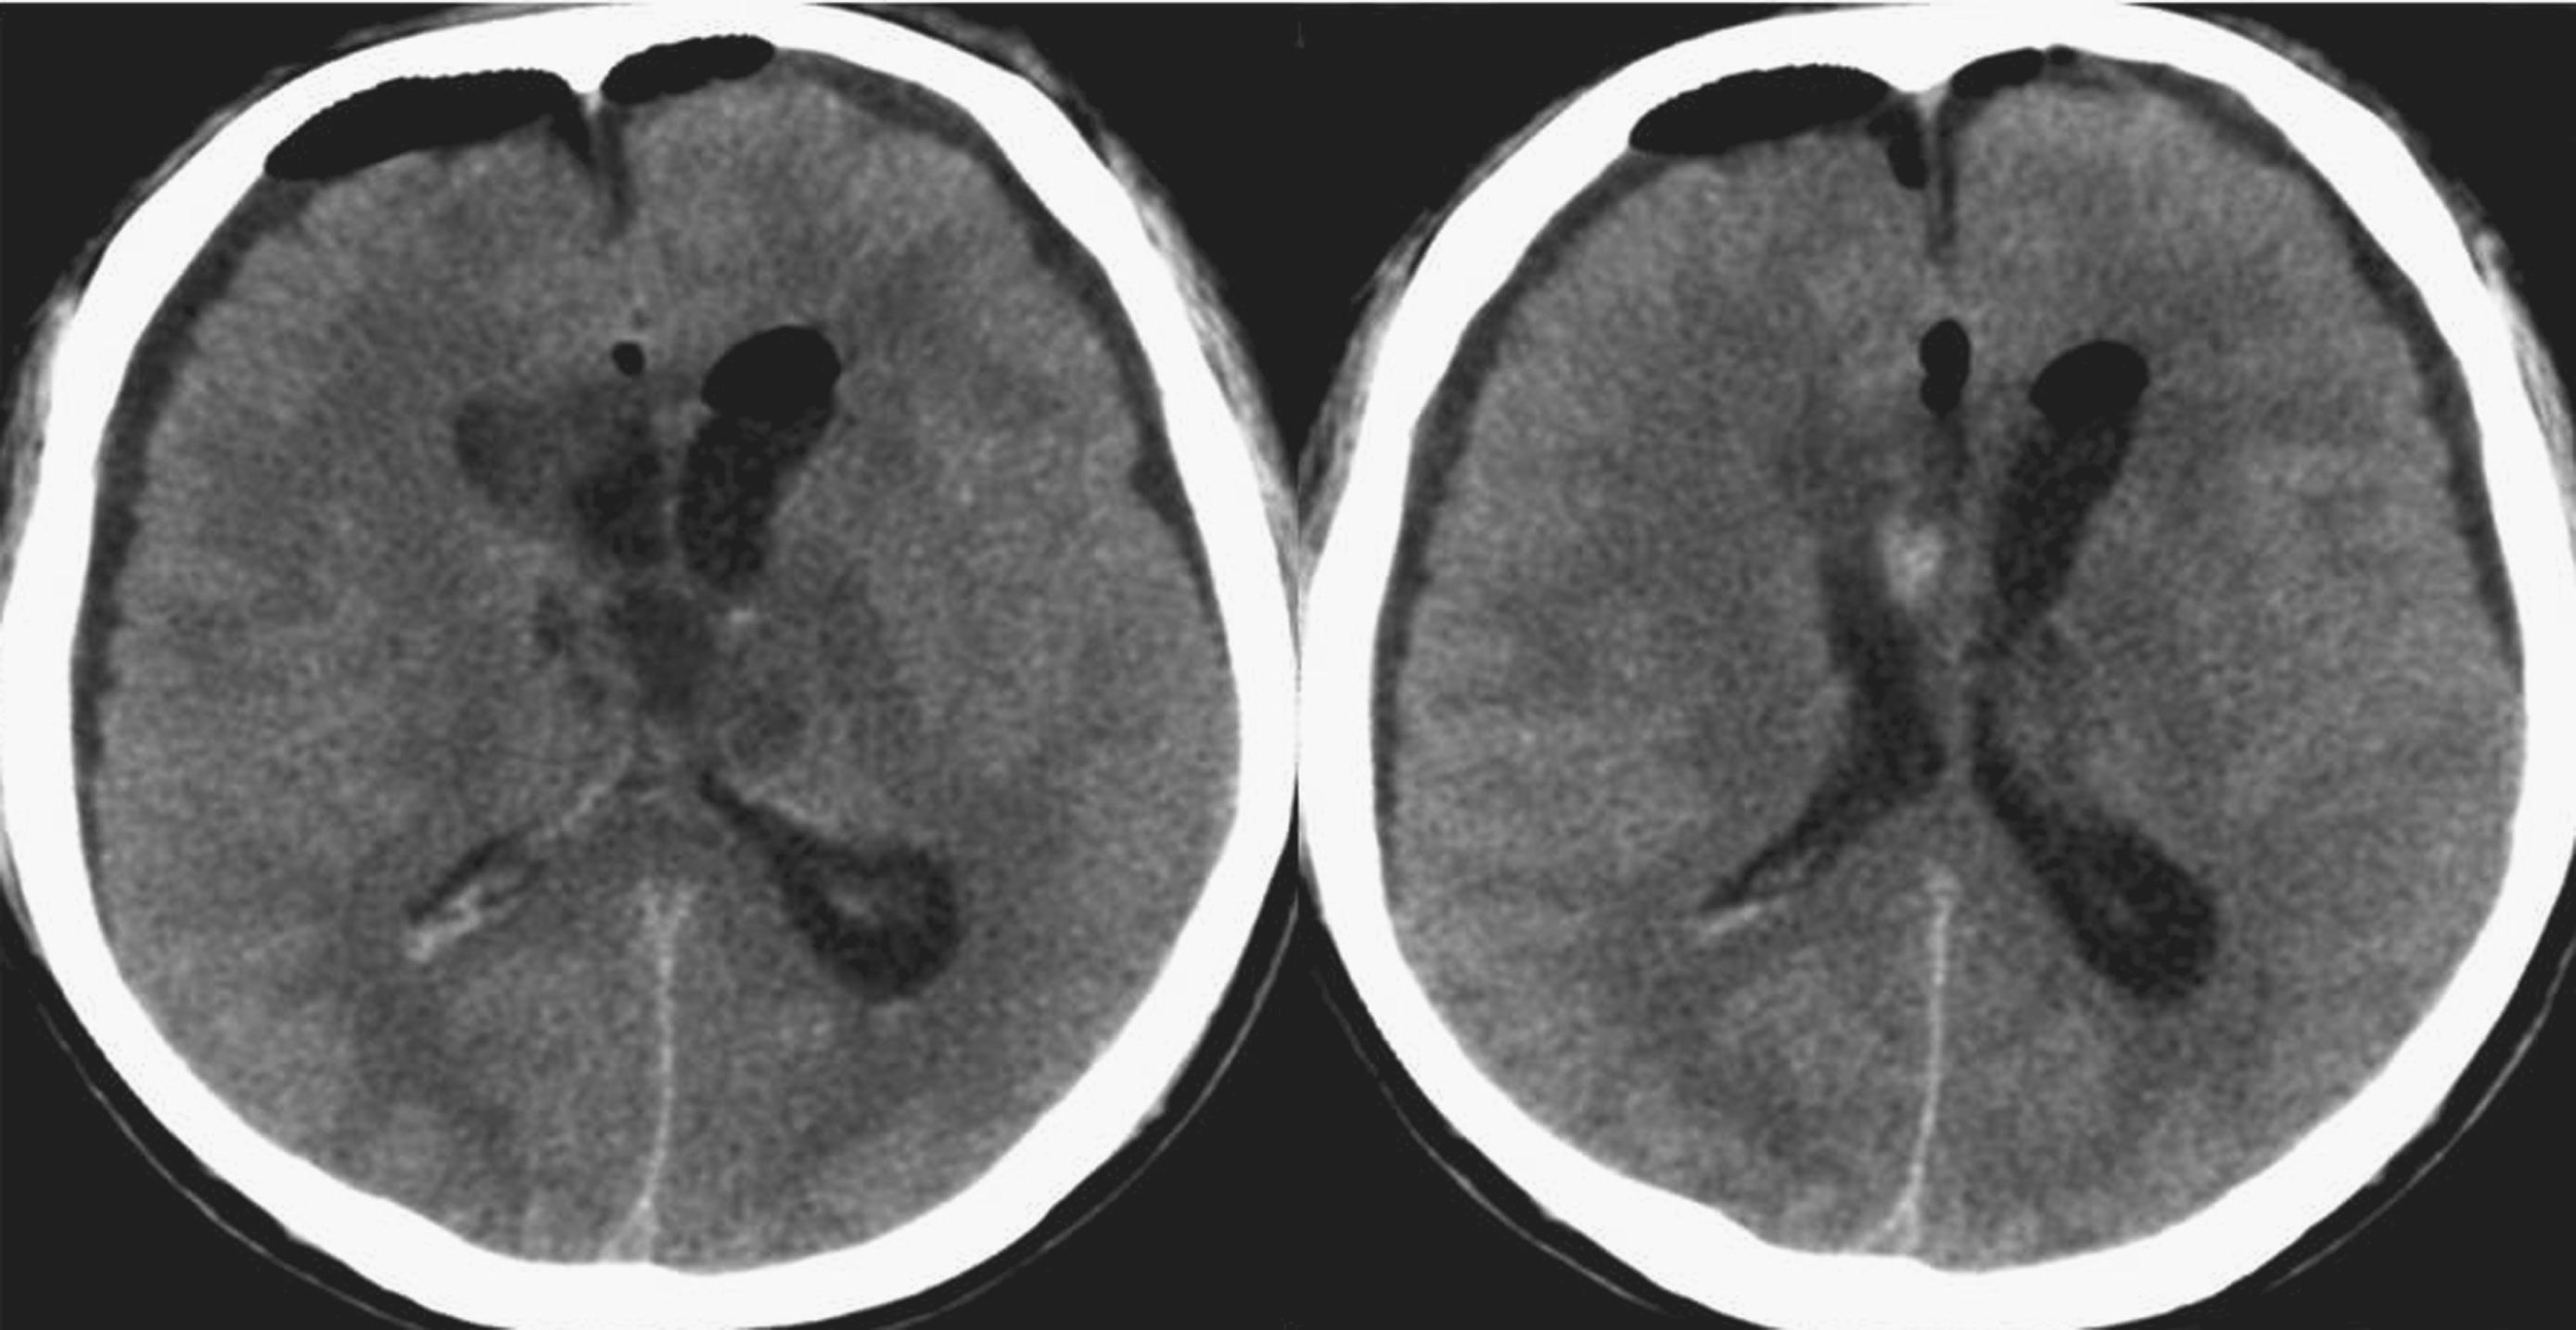

术后查体:神志恍惚,能简单回答问话。双瞳孔等大正圆,直径4.0mm,对光反射灵敏。颈软。四肢自主活动良好,肌张力略高。双侧Babinski征阴性。给予抗炎、脱水及对症治疗。术后24小时内复查头颅CT结果显示脑室系统明显变小(图5-1-4)。术后第3日患者神志清楚,问答合理。双侧脑室引流管通畅。术后第4日完善头颅MRI检查(图5-1-5)。双侧侧脑室外引流术后第6日于全身麻醉下行“经纵裂-胼胝体-穹窿间入路第三脑室内占位病变切除术”。手术过程顺利,复查头颅CT显示完全切除肿瘤,脑室大小基本正常(图5-1-6)。病理检查结果回报:胶样囊肿。患者2周后出院。目前随访恢复良好,未见肿瘤和脑积水复发。

图5-1-4 脑室外引流术后CT表现(引流术后24小时)

图5-1-6 肿瘤切除术后CT表现